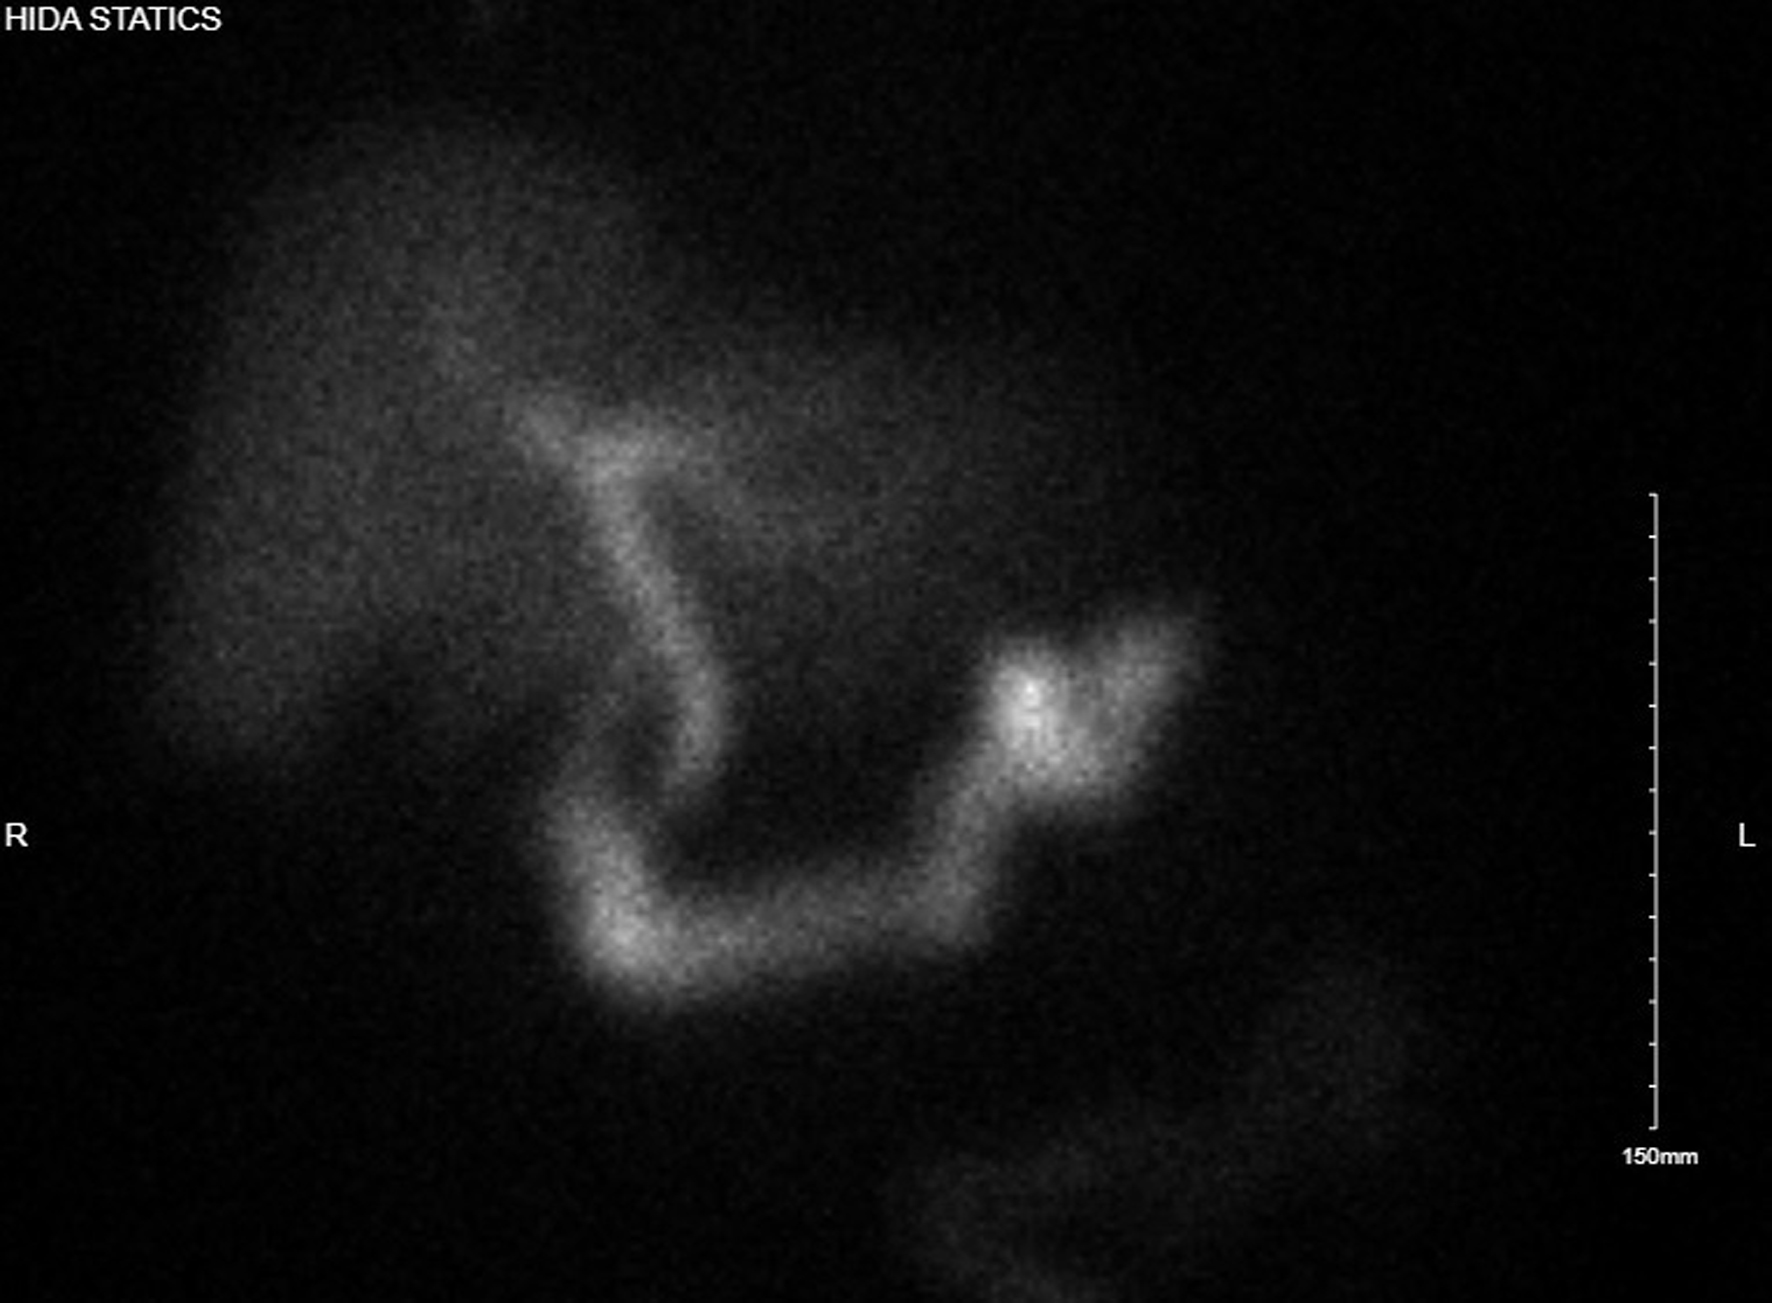

The third day of admission, the patient reported experiencing his first episode of postprandial right upper quadrant pain. A hepatobiliary iminodiacetic acid (HIDA) scan was then performed which showed no uptake of tracer in the gallbladder, consistent with cystic duct obstruction (Fig. 3). Labs again showed no leukocytosis, non-elevated LFTs, and non-elevated lipase (Table 1). With the HIDA scan results and new development of postprandial right upper quadrant pain, a plan was made to perform a laparoscopic cholecystectomy.

Click for large image

Figure 3. Hepatobiliary iminodiacetic acid study with no uptake of tracer in gallbladder, suggesting cystic duct obstruction.